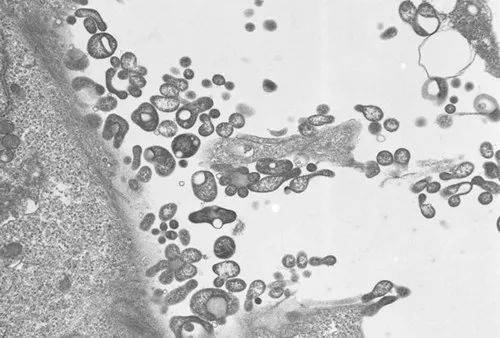

据俄罗斯塔斯社4日报道,世界卫生组织驻俄罗斯代表处负责人巴特尔·别尔德克雷切夫接受媒体采访时说,调查表明,俄罗斯境内没有出现“新病毒感染”,已知病例是由支原体感染引起了肺炎。

别尔德克雷切夫说,针对俄罗斯近来出现的咳血病例,世卫组织联系了俄罗斯相关机构。俄方按世卫组织要求提供了5例在莫斯科和莫斯科州登记的病例数据。经实验室研究确认,这5例病例所患疾病是支原体感染引起的肺炎,不是新病毒感染。